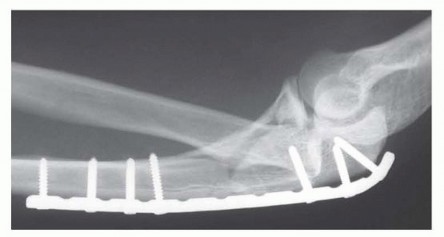

TECH FIG 5 • A. When there is diaphyseal comminution, a temporary external fixator may be useful. B. A long, 3.5-mm limited contact dynamic compression plate is used for fixation. A 22-gauge stainless steel wire is used to enhance fixation of the comminuted olecranon fragments. C. The comminution extending into the diaphysis heals with the bridging plate. The trochlear notch is restored with good elbow function. (B,C: Copyright , MD.)